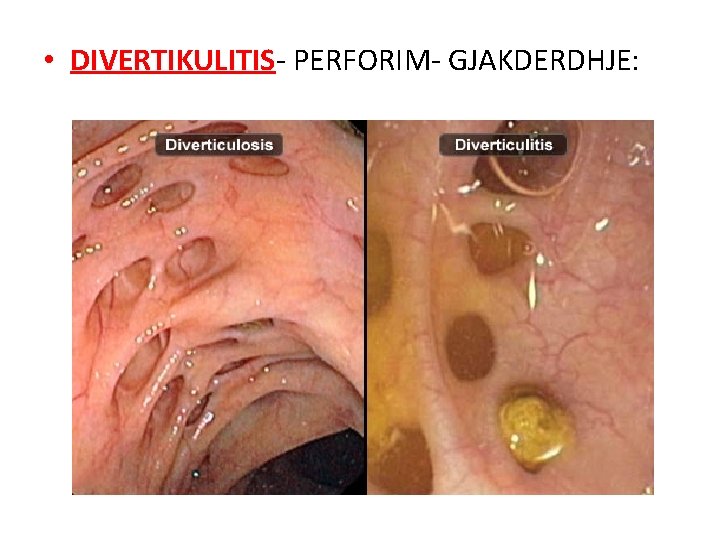

• DIVERTIKULITIS- PERFORIM- GJAKDERDHJE: